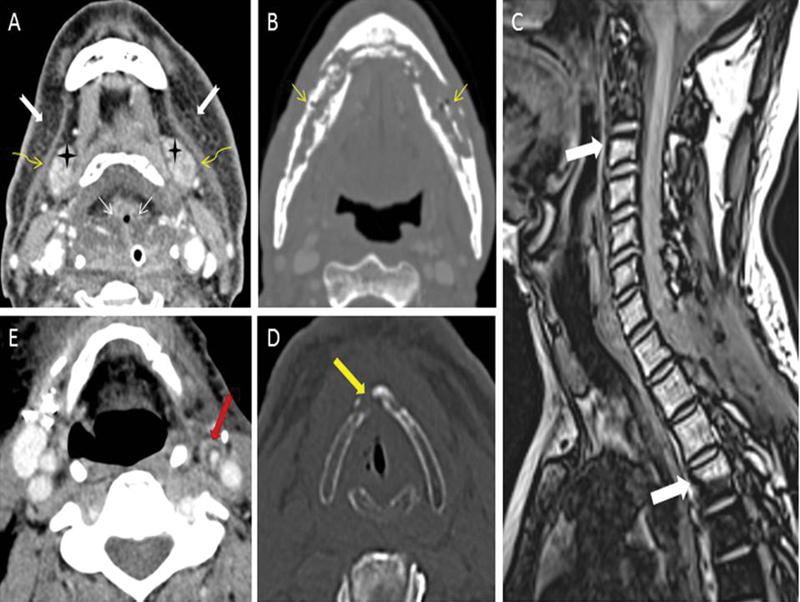

| Figure 2:(A) Expected radiotherapy (RT)-related soft tissue changes. Axial contrast-enhanced computed tomography (CT) image in soft tissue window shows diffuse bilateral symmetrical subcutaneous fat reticulations (notched white arrows), thickened bilateral platysma muscles (curved yellow arrows), increased enhancement of bilateral submandibular glands (black stars), and edema of hypopharyngeal structure (thin straight white arrows). (B) Radiation-induced osteonecrosis. Axial contrast-enhanced CT image in bone window shows bizarre lysis, fragmentation, and sclerosis of the mandible (thin straight yellow arrows). Absence of expansile soft tissue at site of bone destruction rules out the possibility of recurrence. (C) Radiation-induced fatty marrow conversion. Sagittal Dixon T1-weighted fat magnetic resonance (MR) image shows conversion to fatty marrow from C3-D4 vertebrae with sharp margins at mid-C2 and mid-D4 levels (thick white arrows) corresponding with the radiation portal. (D) Radiation-induced chondronecrosis. Axial noncontrast-enhanced CT image in bone window kernel shows lysis of thyroid cartilage (thick yellow arrow) with air foci in the vicinity of the right vocal cord. (E) Radiation-induced atherosclerosis. Axial contrast-enhanced CT image in soft tissue window shows fatty atherosclerotic mural changes in the left external carotid artery (thick red arrow) causing luminal stenosis.

| Figure 2:(A) Expected radiotherapy (RT)-related soft tissue changes. Axial contrast-enhanced computed tomography (CT) image in soft tissue window shows diffuse bilateral symmetrical subcutaneous fat reticulations (notched white arrows), thickened bilateral platysma muscles (curved yellow arrows), increased enhancement of bilateral submandibular glands (black stars), and edema of hypopharyngeal structure (thin straight white arrows). (B) Radiation-induced osteonecrosis. Axial contrast-enhanced CT image in bone window shows bizarre lysis, fragmentation, and sclerosis of the mandible (thin straight yellow arrows). Absence of expansile soft tissue at site of bone destruction rules out the possibility of recurrence. (C) Radiation-induced fatty marrow conversion. Sagittal Dixon T1-weighted fat magnetic resonance (MR) image shows conversion to fatty marrow from C3-D4 vertebrae with sharp margins at mid-C2 and mid-D4 levels (thick white arrows) corresponding with the radiation portal. (D) Radiation-induced chondronecrosis. Axial noncontrast-enhanced CT image in bone window kernel shows lysis of thyroid cartilage (thick yellow arrow) with air foci in the vicinity of the right vocal cord. (E) Radiation-induced atherosclerosis. Axial contrast-enhanced CT image in soft tissue window shows fatty atherosclerotic mural changes in the left external carotid artery (thick red arrow) causing luminal stenosis.